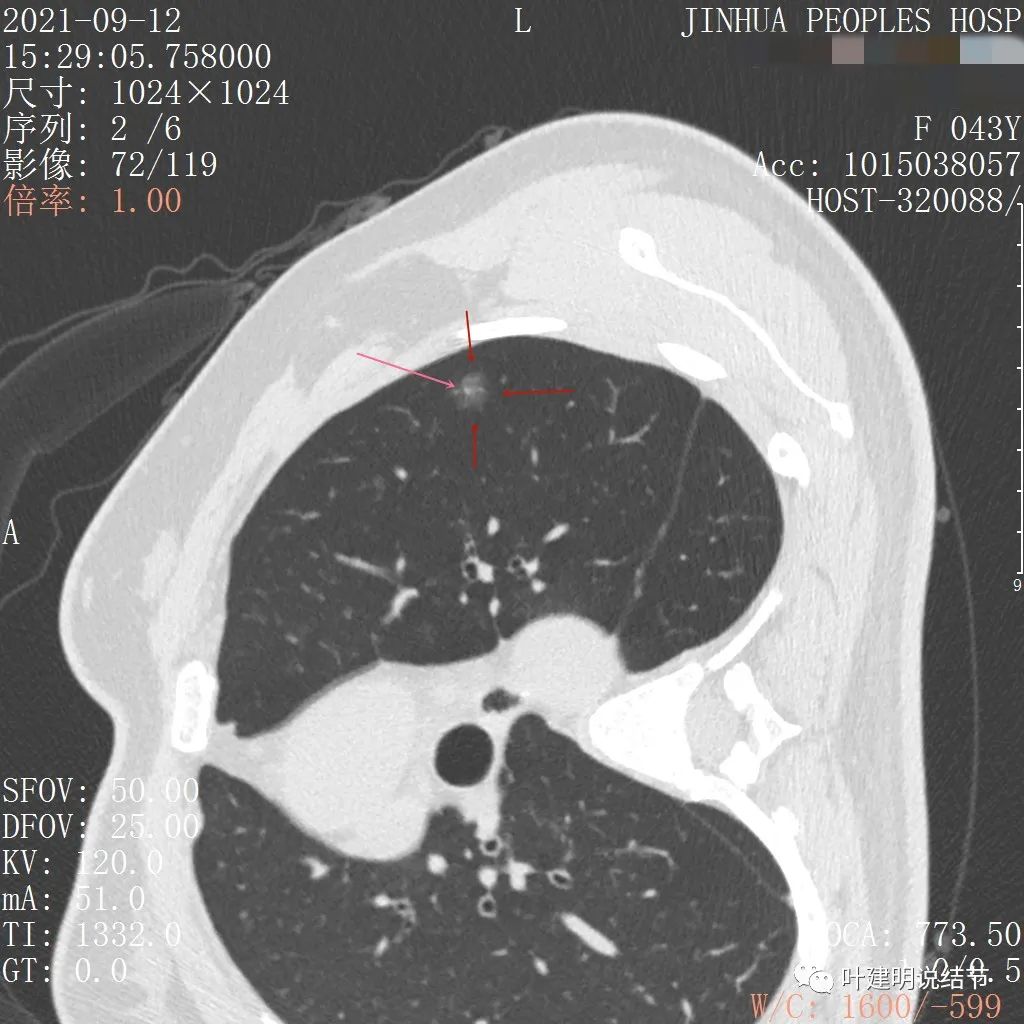

可见左肺上叶磨玻璃结节,边缘略显模糊,瘤肺边界不是很清,但总体上看,病灶轮廓仍是较为清楚的,而且有所层面有微小血管进入,病灶密度也不均匀,感觉有点杂乱。这种病灶如果随访了2个多月仍持续存在,也没多少变化的话,基本上要考虑肿瘤范畴的结节。为了看细节,我们建议其再查了靶扫描,图像如下:

病灶密度较低,膨胀性略,瘤肺边界在靶扫描上还是显得有些清晰的